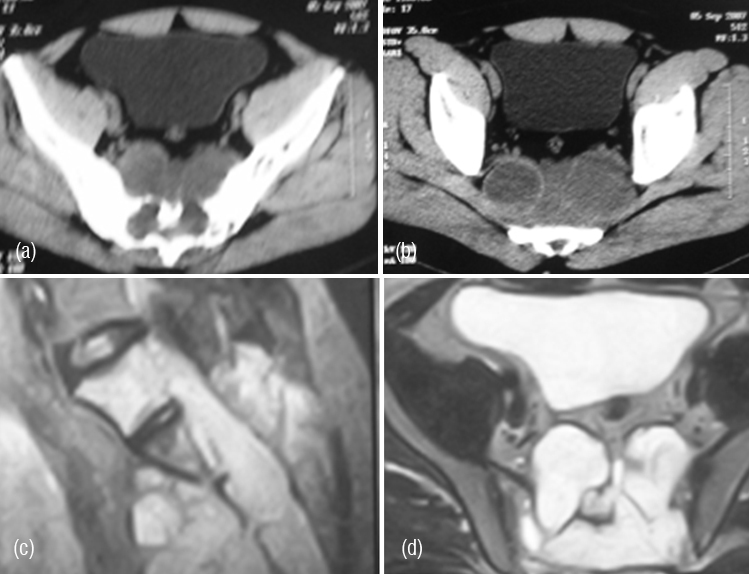

Radiologically, majority of the cases show extensive osteolysis of the sacrum with few areas of osteoblastic reaction. A large soft tissue mass is noted with few calcifications. The calcifications of chondroid nature are common in chondroid type of chordoma and are extensive (Figure 15abcde). In the differential diagnosis, plasmacytoma, metastasis and chondrosarcoma may be considered. Aggressive benign lesions such as aneurysmal bone cyst, myxopapillary ependymoma and aggressive giant cell tumor may also be under consideration particularly when it occurs in the sacrum. In the cervical spine TB of the spine comes under differential diagnosis. Histiologically, the physalipherus cell is characteristic (Figure 15f).

Figure 15: (a) Chordoma of sacrum, (b) Chordoma C. Spine with soft tissue swelling compressing the pharynx , (c) Chordoma C. Spine (d) Chondroid chordoma – AP, (e) lateral of sacrum. (f) Chordoma – Physalipherus cell.